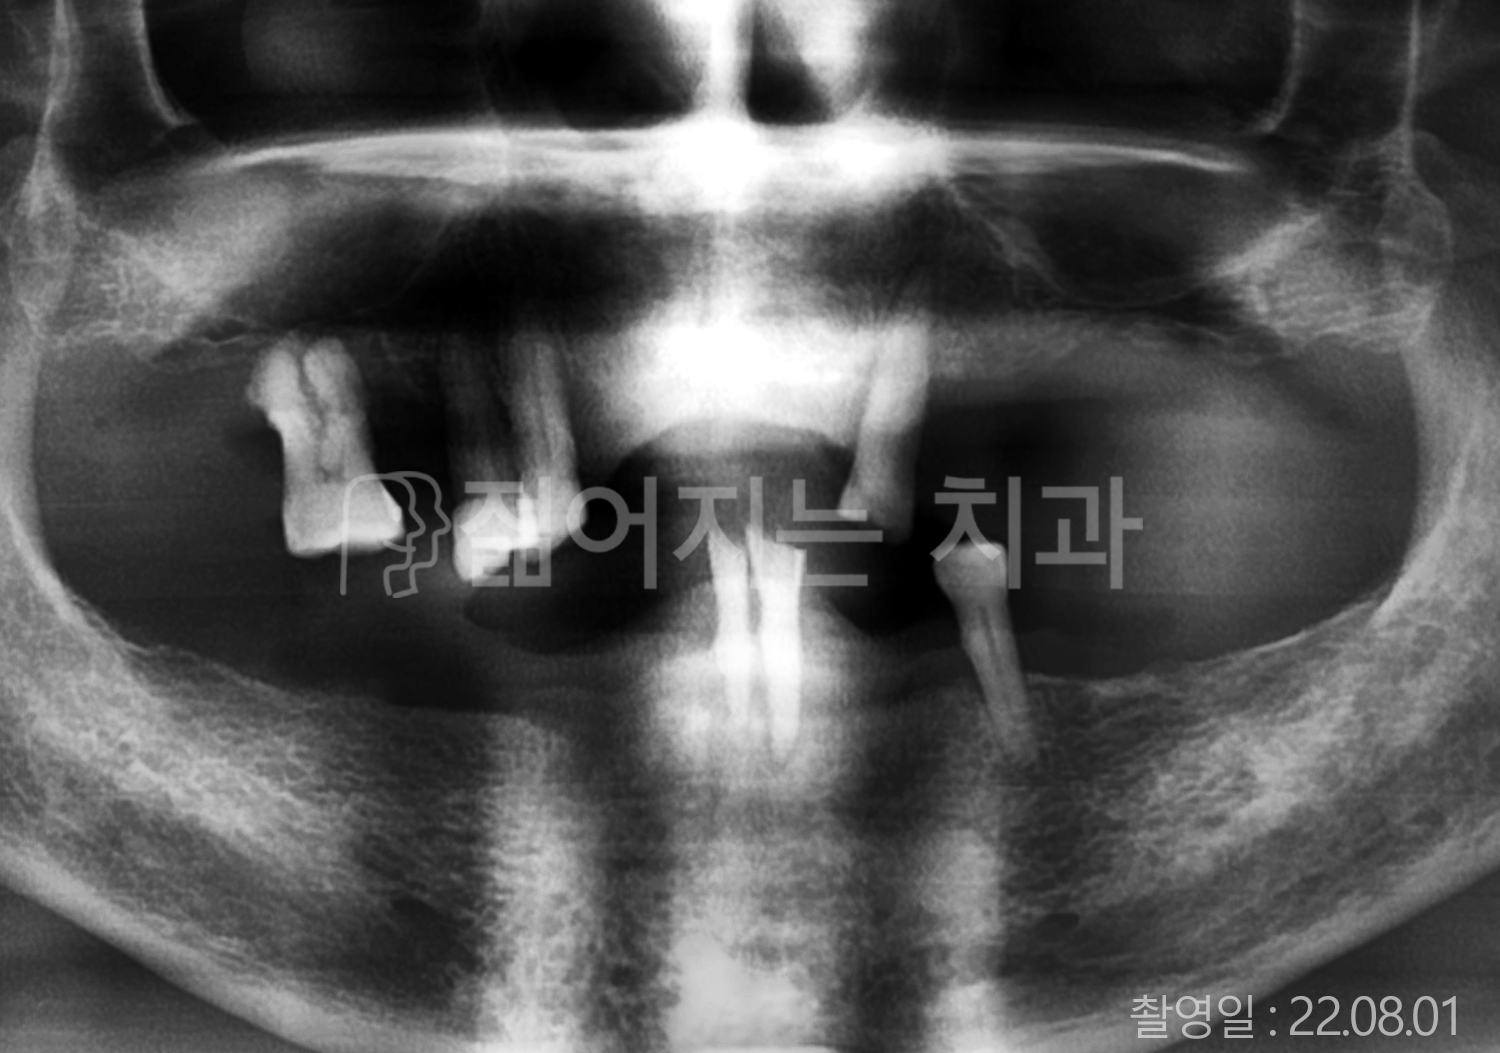

• 50대 고혈압, 당뇨, 고지혈증 전체치아 10개 이상 임플란트

• 60대 골다골증, 간경화 전체치아 10개 이상 임플란트

• 60대 고혈압, 고지혈증 전체치아 10개 이상 임플란트

• 50대 고혈압, 당뇨 전체치아 10개 이상 임플란트

• 60대 고혈압 전체치아 10개 이상 임플란트

• 60대 전체치아 10개 이상 임플란트

• 60대 고지혈증 전체치아 10개 이상 임플란트

• 40대 전체치아 10개 이상 임플란트

• 70대 전체치아 10개 이상 임플란트